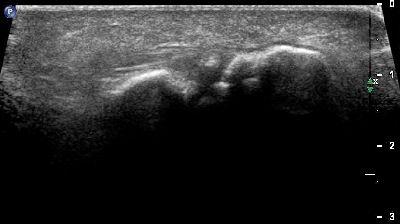

pannicolo fibrotico intrarticolare

(caso del paziente G.V.)